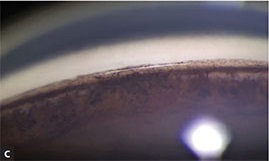

1. 섬유주(Trabecular meshwork, TM)의 색소

섬유주에 색소가 많은 경우는..,

섬유주위아래까지 넓게 색소가 침착이되어 있는 경우가 있습니다.

Ciliary body band부터 Schwalbe line 까지 넓게 착색되어 Trabecular meshwork의 위치를 정확히 어려운 경우가 있습니다.

특히 하부전방각에서 심한데, 이때는 다른 방향의 전방각을 먼저 검사해서, 섬유주의 위치를 먼저 찾고,

그 위치를 바탕으로 하부 전방각에서 위치를 파악하는데 도움을 받아야 합니다.